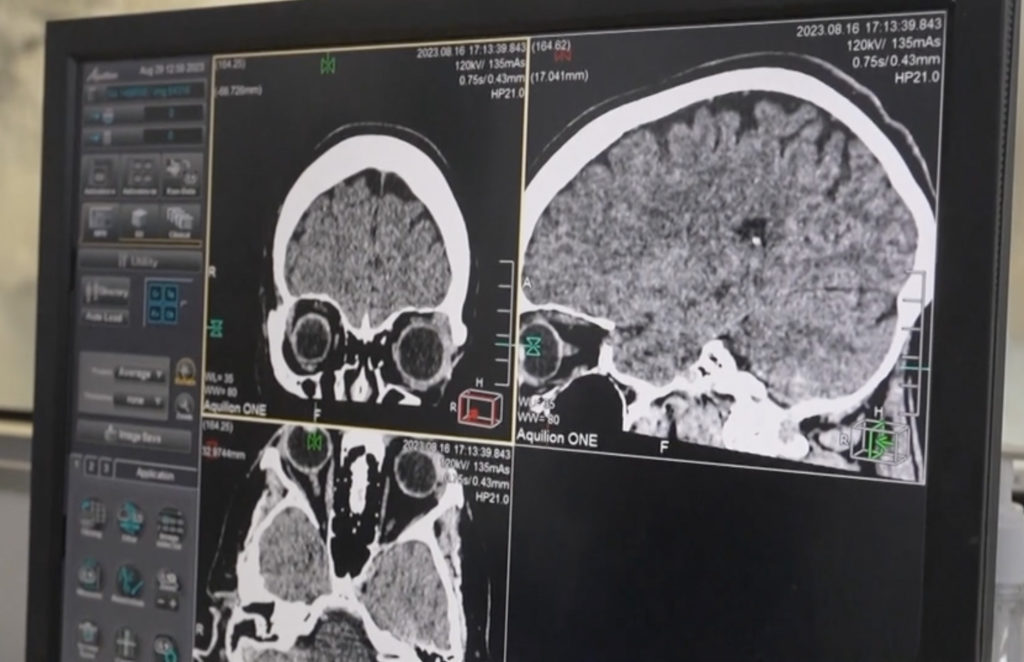

The woman initially sought medical attention due to abdominal pain, diarrhoea, and other symptoms, which gradually escalated to more severe conditions affecting her brain. An MRI scan revealed an anomaly in the right frontal lobe of her brain.